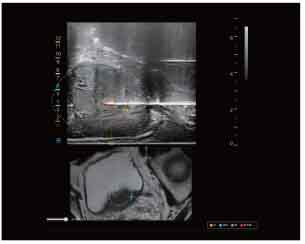

CT-Ultrasound Fusion in PCNL

CT-Ultrasound real-time fusion

3D navigation and tracking